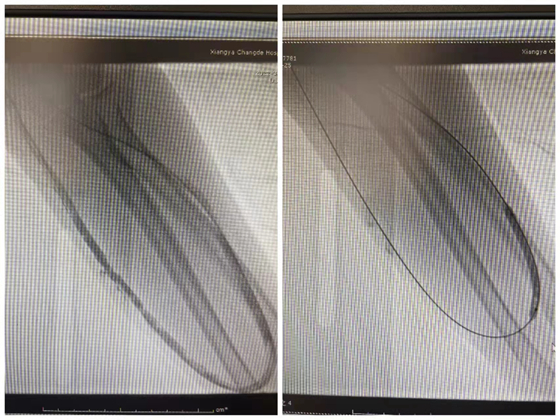

球囊扩张术--重建血管通路的新希望

近日,肾内科联合放射介入科成功进行人造血管球囊扩张术治疗,挽救了其血液透析通路,该技术为广大自身血管条件差及血管资源耗竭的尿毒症患者重建了生命线。

但始料未及的是,近期检查发现刘先生人造血管震颤突然消失,情况危急。这一次,刘先生与家人第一时间来我院就诊,肾内科主任成小苗、副主任医师党智杰立即制定了详细的治疗方案。对刘先生的彩超检查显示左前臂人工血管血栓形成(完全型),与放射介入科副主任医师汤金城合作,根据刘先生具体情况,决定行“左前臂静脉造影+球囊扩张成形术”,术后留置溶栓导管,精准溶解人工血管内血栓。连续三天,人工血管处震颤愈来愈明显。第四天,人工血管血栓消失,并成功穿刺行血液透析治疗。刘先生及其家人喜出望外,竖起了大拇指说道:“感谢湘雅常德医院医护团队对我的救治!”

肾内科主任成小苗指出,患者应在日常生活中保护好自己的生命通道,一旦发现内瘘处震颤、杂音消失或内瘘处疼痛,首先考虑内瘘血栓形成,应立即就医,切勿错过溶栓黄金窗口期。目前,肾内科对于血管通路问题(内瘘血栓形成、内瘘狭窄等)已建立了一套完善的治疗方案,并积累了丰富的经验。